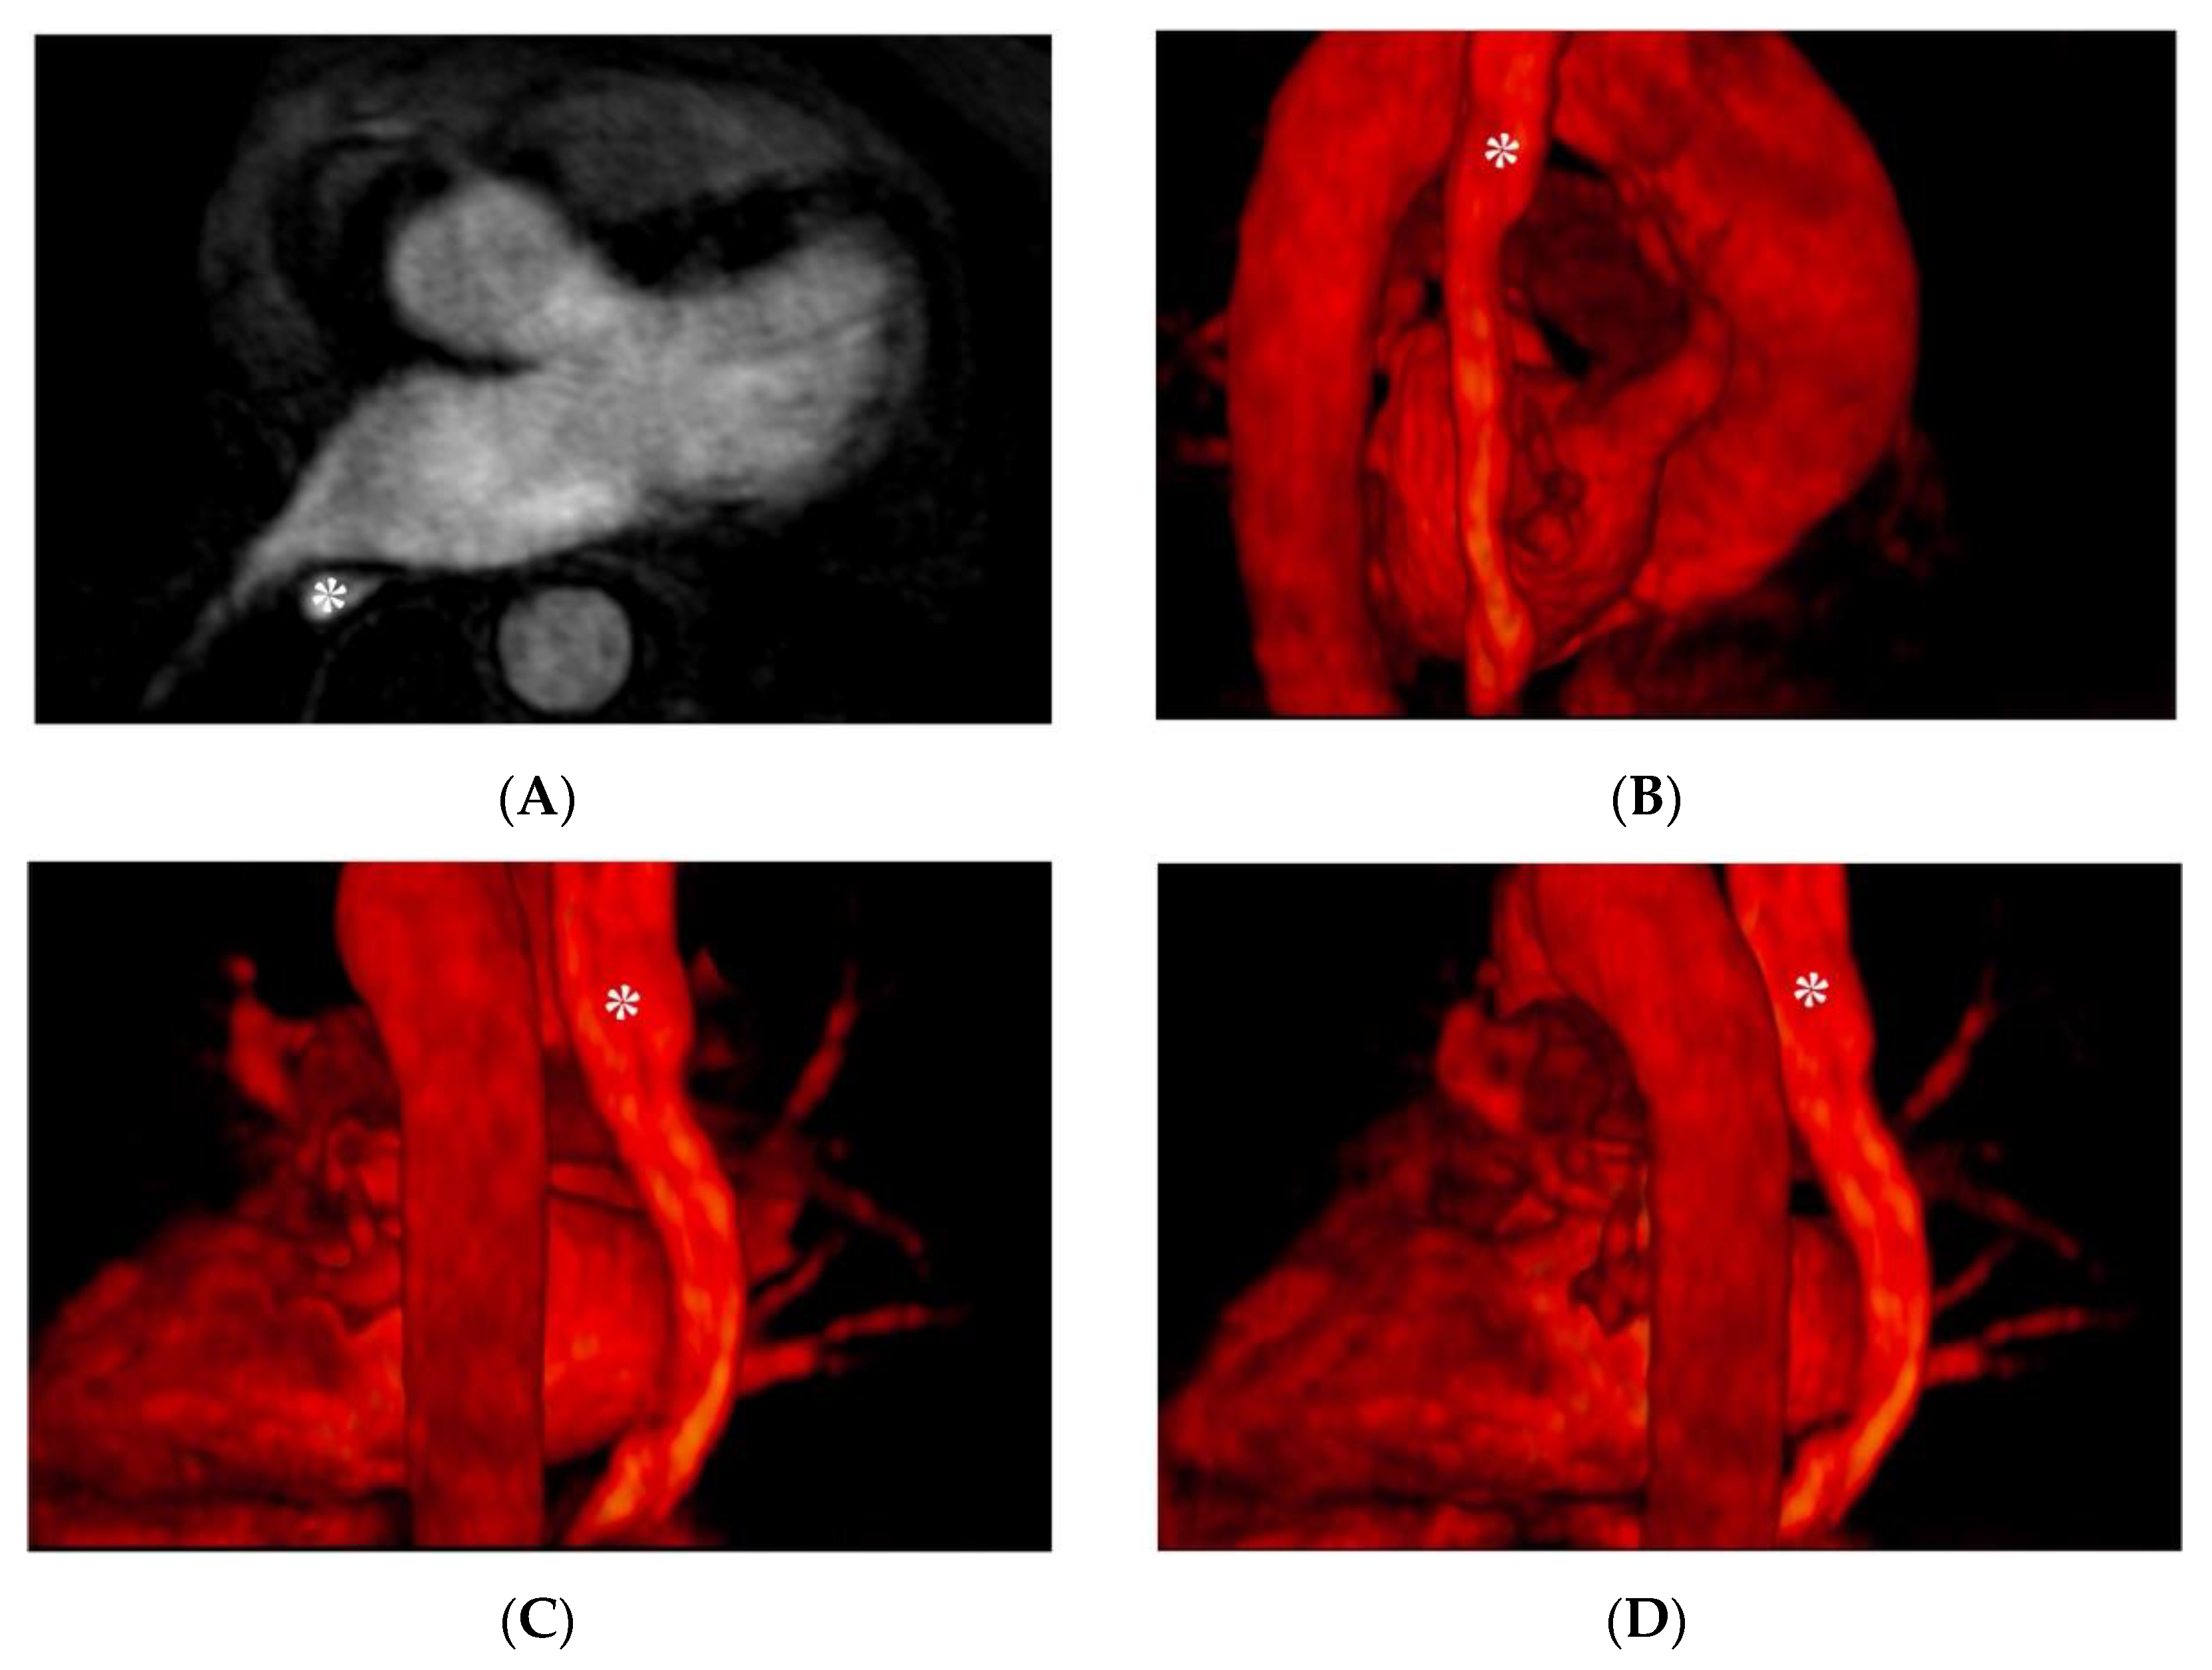

7. Cardiac Adipose Tissue

- Ciuffo, L.; Nguyen, H.; Marques, M.D.; Aronis, K.N.; Sivasambu, B.; de Vasconcelos, H.D.; Tao, S.; Spragg, D.D.; Marine, J.E.; Berger, R.D.; et al. Periatrial Fat Quality Predicts Atrial Fibrillation Ablation Outcome. Circ. Cardiovasc. Imaging 2019, 12, e008764. [Google Scholar] [CrossRef]

- Bonou, M.; Mavrogeni, S.; Kapelios, C.J.; Markousis-Mavrogenis, G.; Aggeli, C.; Cholongitas, E.; Protogerou, A.D.; Barbetseas, J. Cardiac Adiposity and Arrhythmias: The Role of Imaging. Diagnostics 2021, 11, 362. [Google Scholar] [CrossRef] [PubMed]

- Nakamori, S.; Nezafat, M.; Ngo, L.H.; Manning, W.J.; Nezafat, R. Left Atrial Epicardial Fat Volume Is Associated With Atrial Fibrillation: A Prospective Cardiovascular Magnetic Resonance 3D Dixon Study. J. Am. Heart Assoc. 2018, 7, e008232. [Google Scholar] [CrossRef]

| Dixon chemical shift imaging | 3D navigator gated mDIXON | To quantify pericardial/periatrial fat |